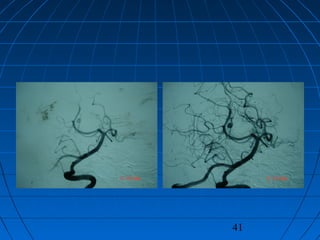

 A Y: 33yaşında kadın hastaA Y: 33yaşında kadın hasta

 Şiddetli başağrısıŞiddetli başağrısı (son bir gün içinde)(son bir gün içinde)

 Nörolojik muayene:Nörolojik muayene:

ES-MİB ++, E3M6V4 (GKS 13)ES-MİB ++, E3M6V4 (GKS 13)

 WFNS 2WFNS 2

 Fisher 3Fisher 3

CERRAHİCERRAHİ

 Sağ lateral infratentorialSağ lateral infratentorial

supraserebellar - retrosigmoidsupraserebellar - retrosigmoid

yaklaşımyaklaşım

 SCA Anevrizması kliplendi.SCA Anevrizması kliplendi.